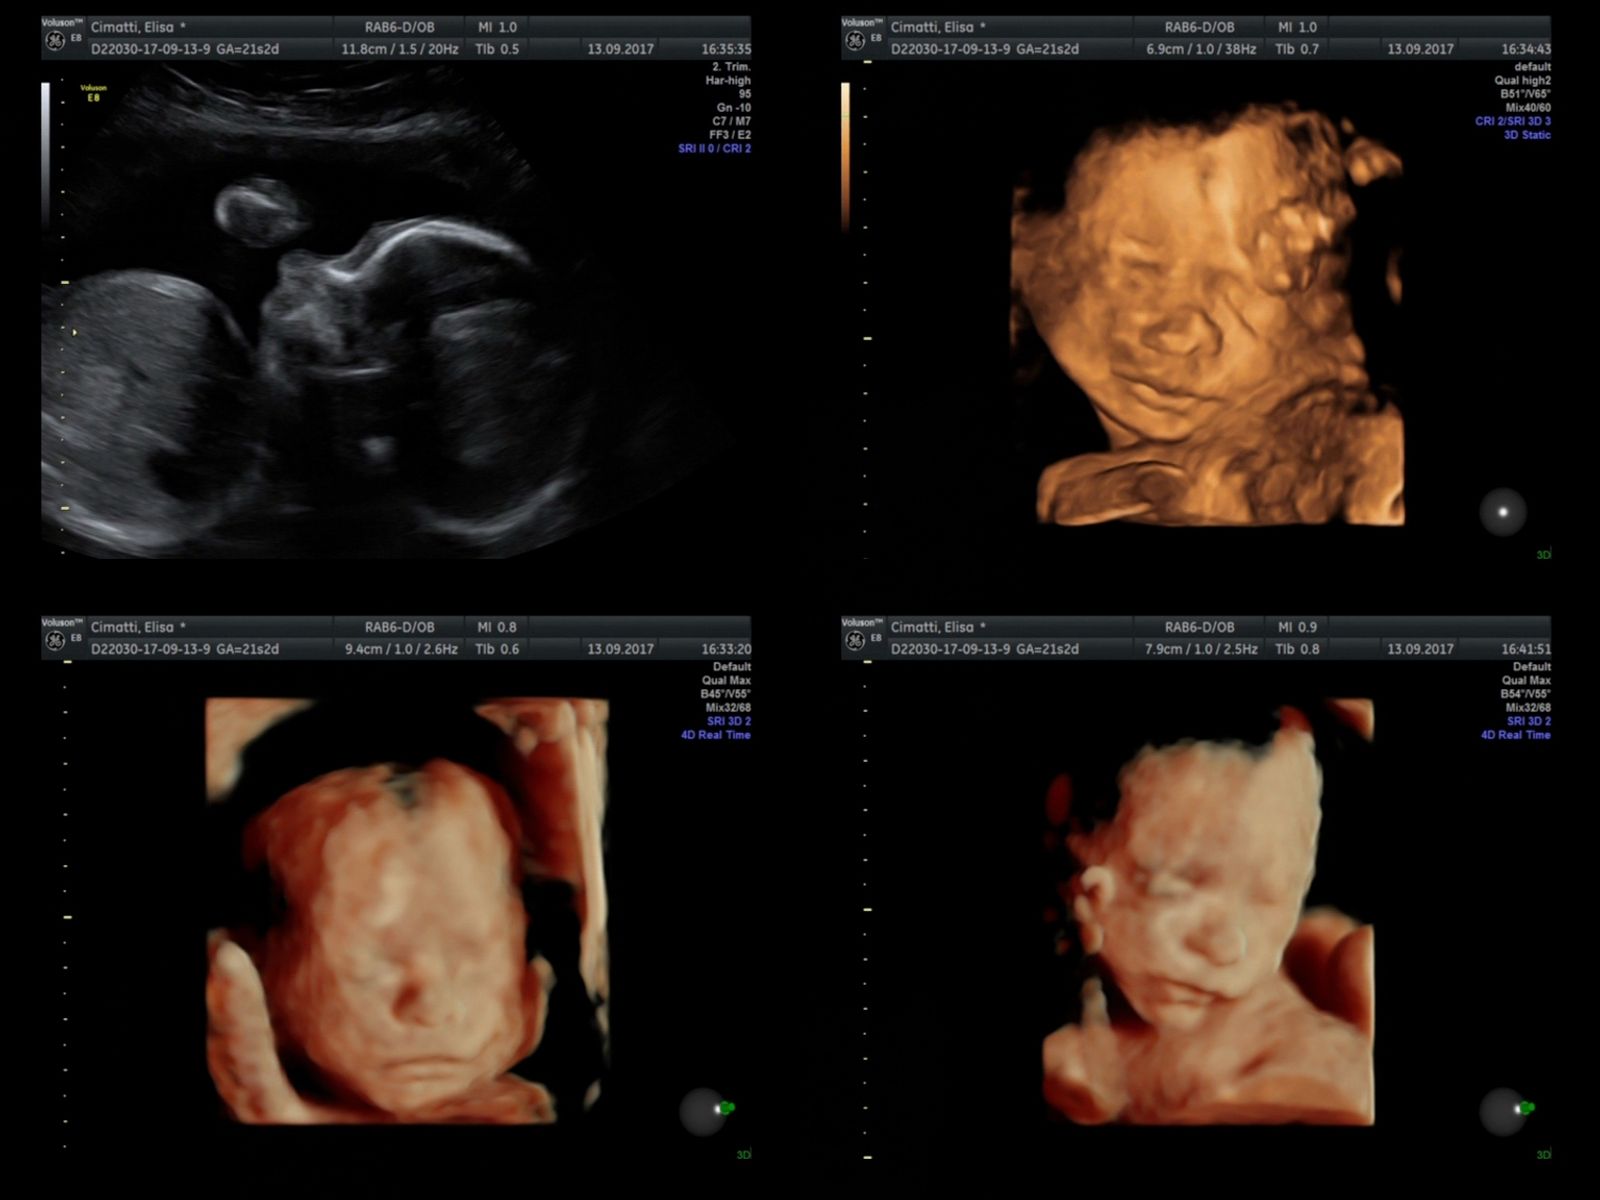

© Filippo Venturi - Image from the He looks like you photography project

Three-dimensional echography (computerised reconstruction and processing of two-dimensional ultrasound images) of my son Ulisse, 4 months before his birth. September 13, 2017.